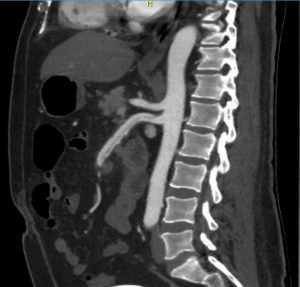

Mesenteric ischemia CT angiogram

Sagittal view of a CT angiogram demonstrating atherosclerosis at the ostium of the celiac artery and SMA